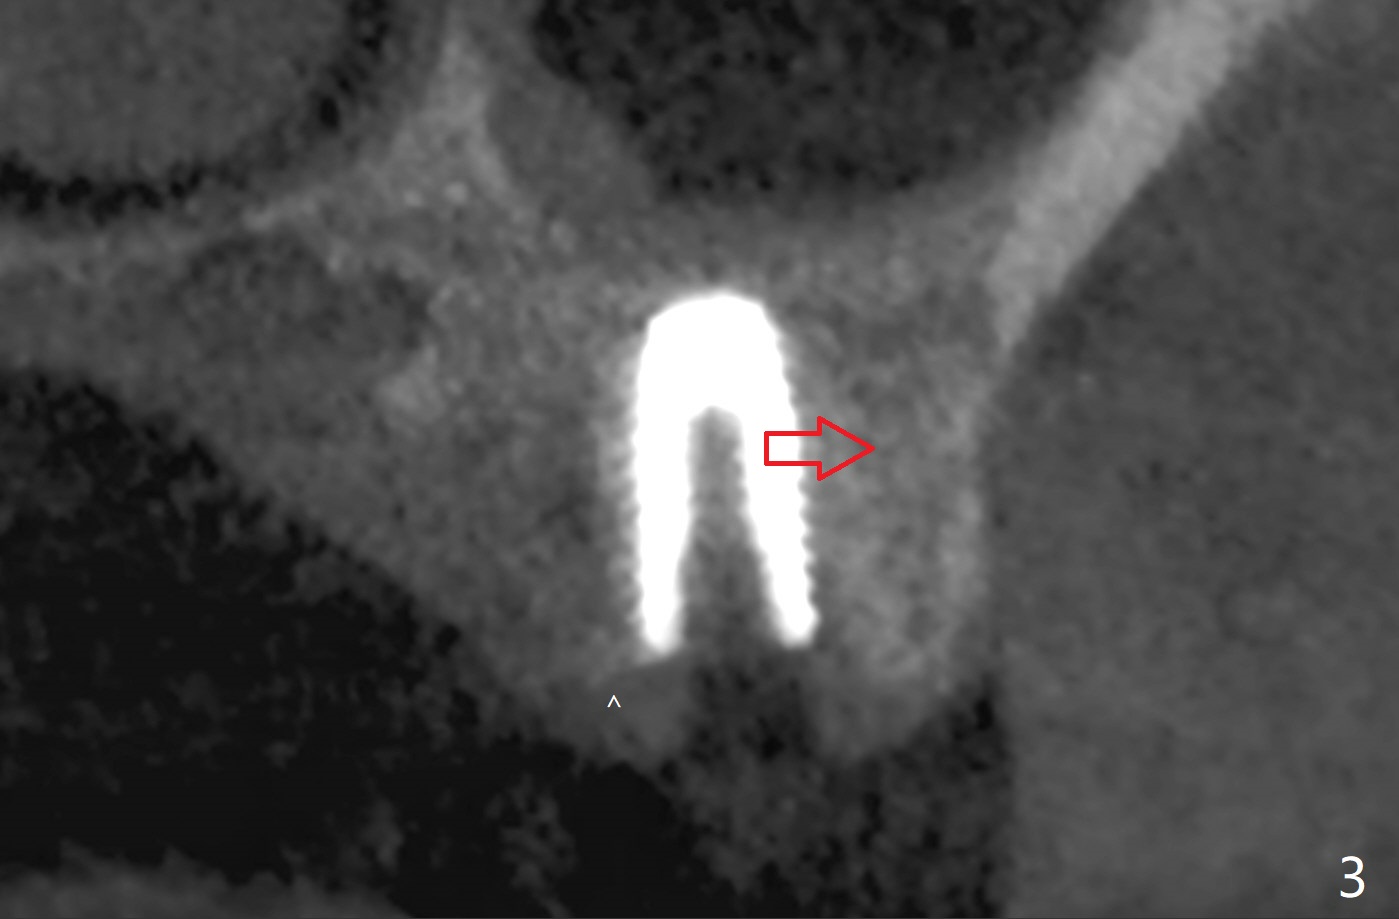

Low bone density is confirmed during osteotomy at #14 (6 months post socket preservation).  Underprep is adopted: after use of 3.5x10 mm drill instead of 4.5x10 mm one, a 4x10 and 4.5x10 mm dummy implant are placed for bone condensation.  When a 5x10 mm definitive implant is placed, it is unable to be placed to the depth.  After use of 4.0x10 mm, the final implant reaches depth ~ 1 mm more than planned.  But there appears no bone palatal to the implant clinically.  Small-field CT is taken.  In fact there is crestal bone palatal to the implant, but in small amount and in low bone density (Fig.1,2).  The implant should have been designed to be placed more buccal (Fig.3 arrow).  The implant also looks to be placed too close the root of the tooth #13, probably related to the rotation of #13 (Fig.4).  Unfortunately the patient does not agree to have limited orthodontics.  After palatal bone graft, GEM Cap is used to close the access with periodontal glue (Fig.5).  Spacer/periodontal dressing should have been used.  The wound heals 8 months postop, but 2-3 palatal threads are exposed with uncover.  After 6 mm profile drill and placement of a 6x4 mm healing abutment, allograft is placed palatal (Fig.6).  Upper Molar Immediate Implant, Trajectory II Shield Next Case of Buccal Defect  SP Xin Wei, DDS, PhD, MS 1st edition 11/19/2019, last revision 09/19/2020